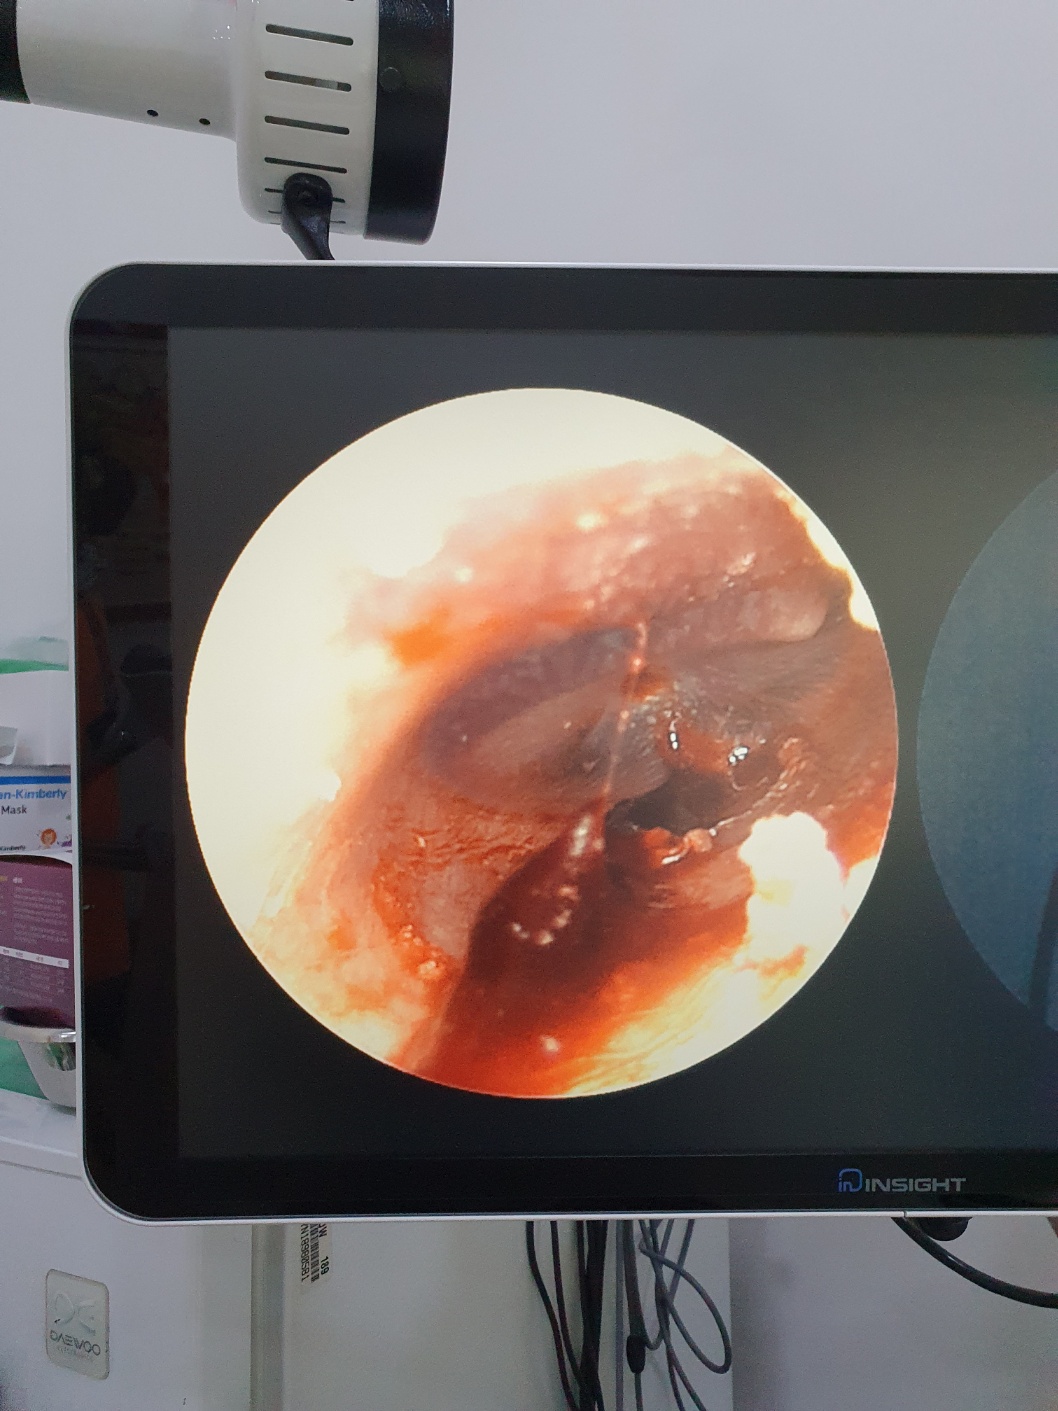

"귀!!! 귀에서 피!!!!!!!"

ㅎ ㅏ............. 영화나 만화 속에서만 보던 그 장면이었습니다.

소리공격을 당하거나 그럴 때 귀에서 피가 흐르는 장면을 화면속에서만 본적이 있는데

정말... 영화의 한장면처럼 귓속에서 피가 흘러 나오고 있었습니다.

경황이없어서 귀에서 흐르는 피사진 찍을 생각도 못했습니다.

다급하게 아이를 감싸안고 바로 응급실로 달려갔습니다.

자초지종을 설명드리니 큰문제가 있다면 구토를 하거나 아이가 힘이없어야하는데

아이가 의사표현도 똑바로하고(귀 절대로 안보여줌, 무섭다고 악지르고 난리가나서 귀를 보실 수 없었음)

정신이 온전 한 것 같아 보이기 때문에 날이 밝으면 이비인후과에 한번 가보라고 안내를 받았습니다.

그렇게 이비인후과에서 둘째의 차례가 됐고, 들어갔습니다.

그녀석은 역시나 비협조적이었으나 어르고 달래가며, 힘들게 진료를 보았습니다.

그렇게 생각치도 못한이야기를 듣게되었습니다.ㅠ